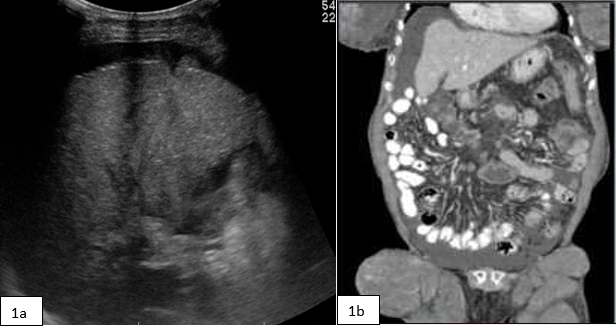

A 81 years female reported for CT scan of abdomen for liver cirrhosis ...

Read More